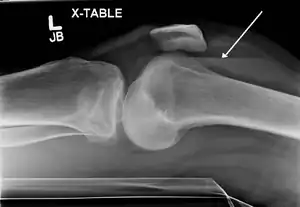

Lipohemarthrosis due to a tibial plateau fracture -

A tibial plateau fracture seen on X-ray